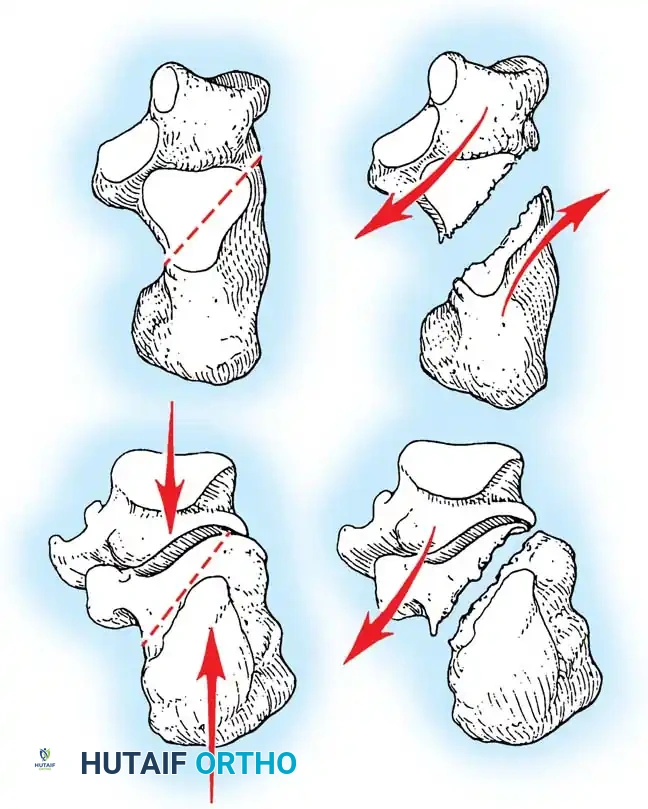

Cadaveric studies, anatomical dissections, and advanced computed tomography (CT) have elucidated the precise mechanism of intraarticular calcaneal fractures. The contact point of the calcaneus with the ground is situated lateral to the primary weight-bearing axis of the lower extremity.

When an axial load is applied, the lateral process of the talus acts as a wedge, driving into the crucial angle of Gissane. Shear forces are directed through the posterior facet toward the medial wall of the calcaneus.

The Primary Fracture Line

This shear force creates the primary fracture line, which is almost universally present. It extends from the proximal, medial aspect of the calcaneal tuberosity, obliquely through the anterolateral wall, typically exiting near the crucial angle of Gissane. The position of this line through the posterior facet is variable; it may occur in the medial third (near the sustentaculum tali), the central third, or the lateral third.

As the axial force continues, the medial spike of the sustentacular fragment is driven medially, threatening the neurovascular bundle, while secondary fracture lines propagate through the posterior facet.

Essex-Lopresti classically described two distinct patterns based on the exit point of the secondary fracture line:

- Joint Depression Type: The secondary fracture line exits posterior to the posterior facet but anterior to the Achilles tendon insertion. The articular fragment is driven deep into the cancellous body of the calcaneus.

- Tongue Type: The secondary fracture line exits posterior to the Achilles tendon insertion. The posterior facet remains attached to the posterior tuberosity, creating a single, large "tongue" piece that rotates dorsally.

Surgical Warning: As the talus impacts the calcaneus, it blows out the lateral wall, severely compressing the subfibular space. This leads to peroneal tendon impingement or dislocation. Furthermore, the medial spike is driven deep into the medial soft tissues. Medially open fractures require meticulous deep dissection to expose, irrigate, and debride this medial spike; superficial skin debridement is grossly inadequate.